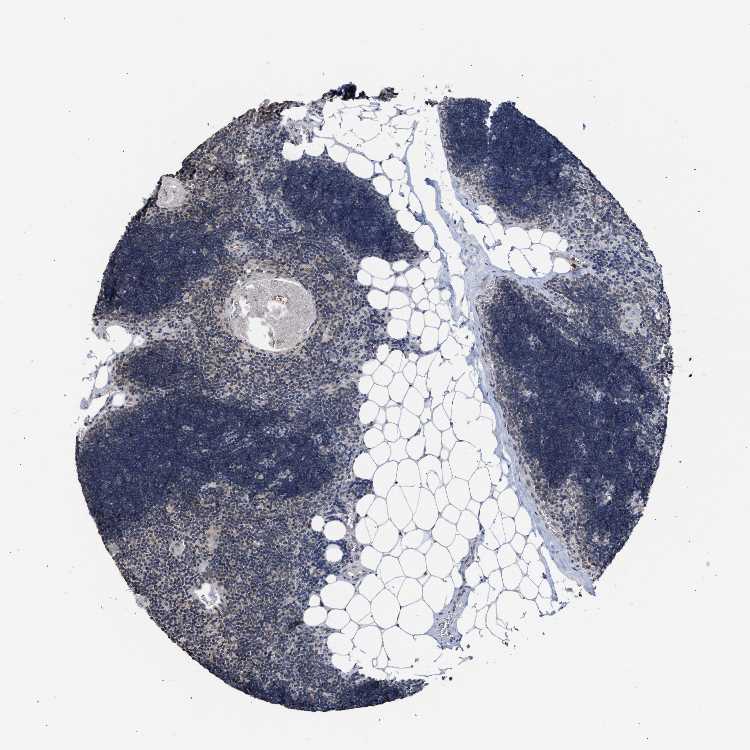

TISSUE PRIMARY DATA LYMPH NODE Show tissue menu

LYMPH NODE - Antibody stainingi

Antibody staining in the annotated cell types in the current human tissue is reported as not detected, low, medium, or high, based on conventional immunohistochemistry profiling in selected tissues. This score is based on the combination of the staining intensity and fraction of stained cells.

Each image is clickable and will lead to virtual microscopy that enables deeper exploration of all samples and also displays staining intensity scores, fraction scores and subcellular localization as well as patient and tissue information for each sample.

Antibody CAB019271

Germinal center cells Low

Non-germinal center cells Not detected